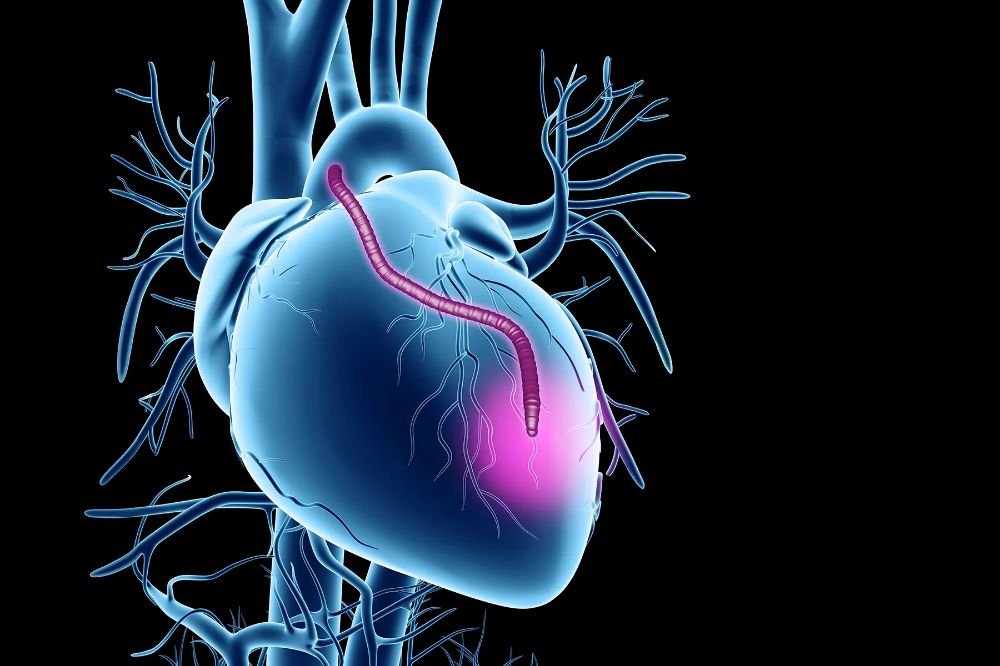

Liver Transplant

Liver transplant is performed for patients suffering from liver cirrhosis, liver failure, or liver cancer. India offers advanced surgical techniques with high success rates.

Multi-Organ Failure Management

Specialized hospitals in India also manage complex cases involving multiple organ dysfunction using advanced critical care systems